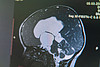

IMG_20221215_105257_858IMG_20221215_105258_024

IMG_20221215_105257_858.